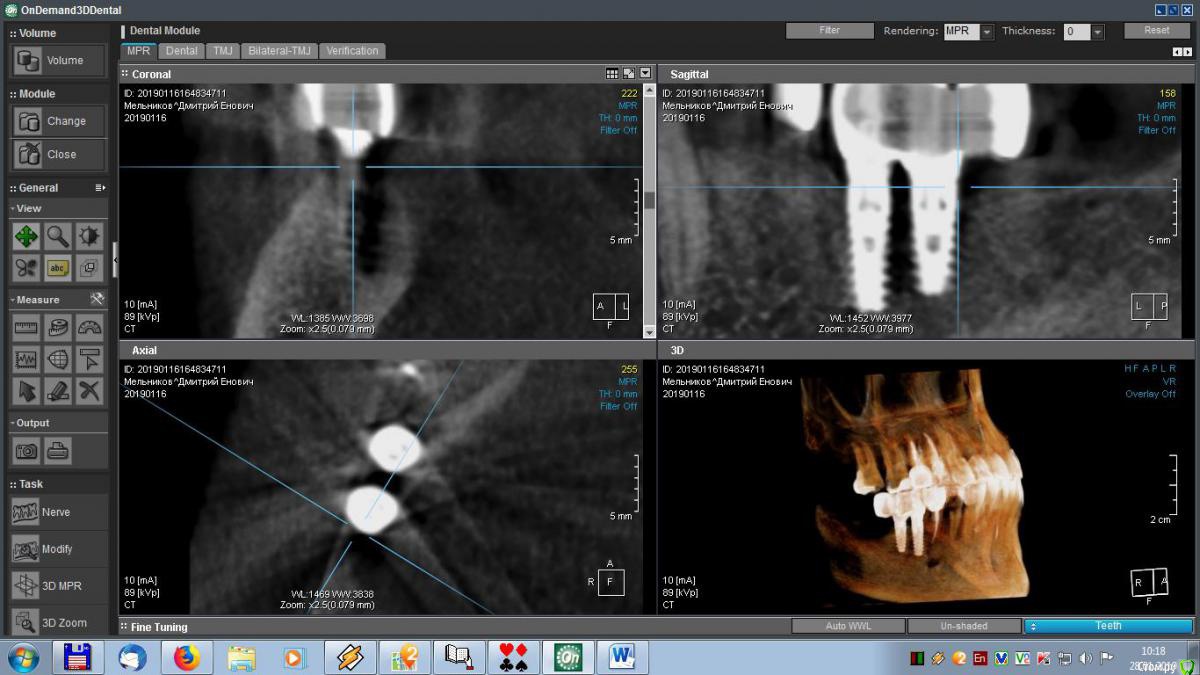

meld Опубликовано 29 января, 2019 Автор Поделиться Опубликовано 29 января, 2019 Здравствуйте, уважаемые доктора! Скоро год, как мне поставили метало-керамические коронки. До сих пор я ощущаю зуд в области имплантатов. На контрольном приеме врач ничего криминального не увидел, прописал чистку, фотосан и КТ, Я все сделал, по КТ врач сказал, что все нормально. Посмотрите, пожалуйста, мои среза и подтвердите (или нет) - все ли нормально. Спасибо. Ссылка на комментарий

meld Опубликовано 29 января, 2019 Автор Поделиться Опубликовано 29 января, 2019 Выложил больше срезов. Спасибо. Ссылка на комментарий